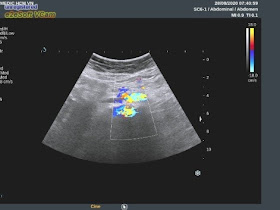

At Medic Center, vascular ultrasound revealed aliasing

spectrum of  right common iliac artery in stenosis

# 80% due to atherosclerosis.

Right common femoral artery shows Doppler spectral biphasic

pattern.